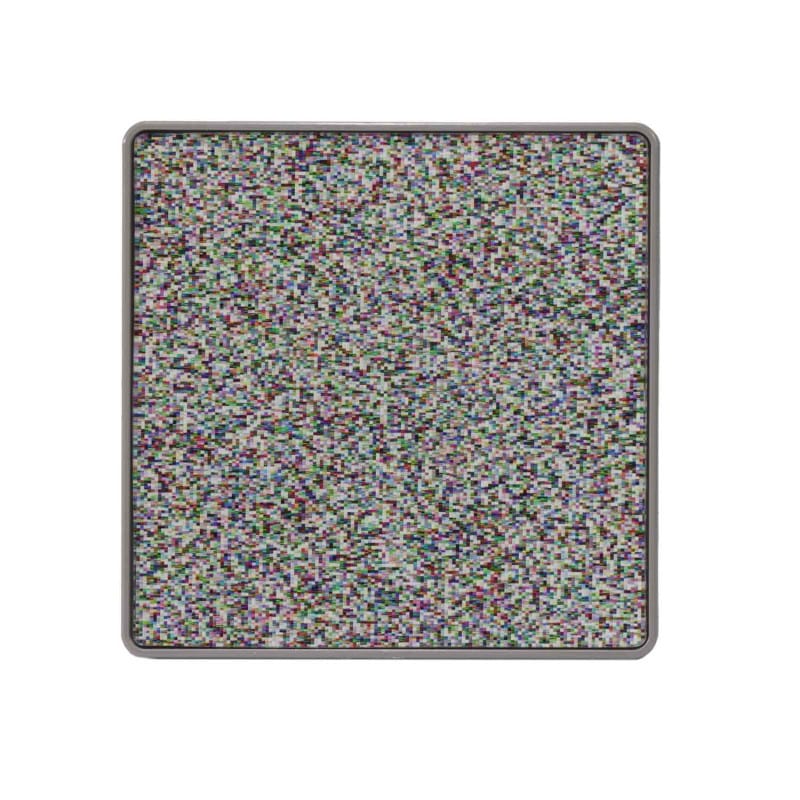

The magnetic test cards can be arranged and displayed individually or in groups on the red test panel. The objects on the test cards are perfectly camouflaged - both when viewed with one eye and with the lens grid running horizontally. Due to its special mode of operation, the test is ideally suited for simple screening, determining the stereo threshold or screening with the Preferential Looking method. In addition, the test can be performed without test glasses and guessing the objects is not possible.

- Cards with one 3D random dot stereo object each

- Test objects perfectly camouflaged